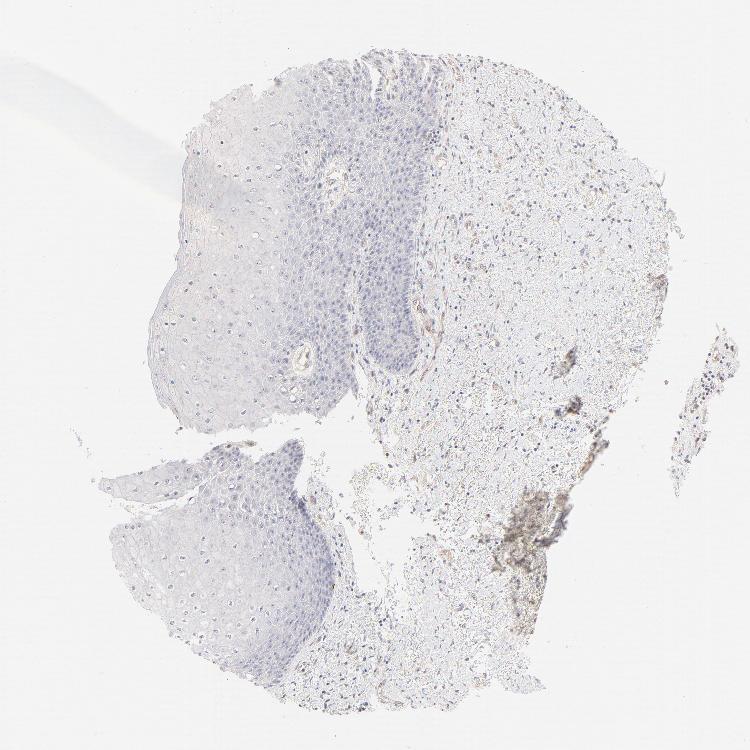

SKIN 2 - Antibody stainingi

Antibody staining in the annotated cell types in the current human tissue is reported as not detected, low, medium, or high, based on conventional immunohistochemistry profiling in selected tissues. This score is based on the combination of the staining intensity and fraction of stained cells.

Each image is clickable and will lead to virtual microscopy that enables deeper exploration of all samples and also displays staining intensity scores, fraction scores and subcellular localization as well as patient and tissue information for each sample.

Antibody HPA003316Antibody HPA003479

Cells in basal layer -Not detected

Cells in corneal layer -Not detected

Cells in granular layer -Not detected

Cells in spinous layer -Not detected

Endothelial cells -Not detected

Epidermal cells Low-

Extracellular matrix -Not detected

Fibrohistiocytic cells -Not detected

Hair follicles -Not detected

Langerhans cells -Not detected

Lymphocytes -Not detected

Melanocytes -Not detected

Vascular mural cells -Not detected